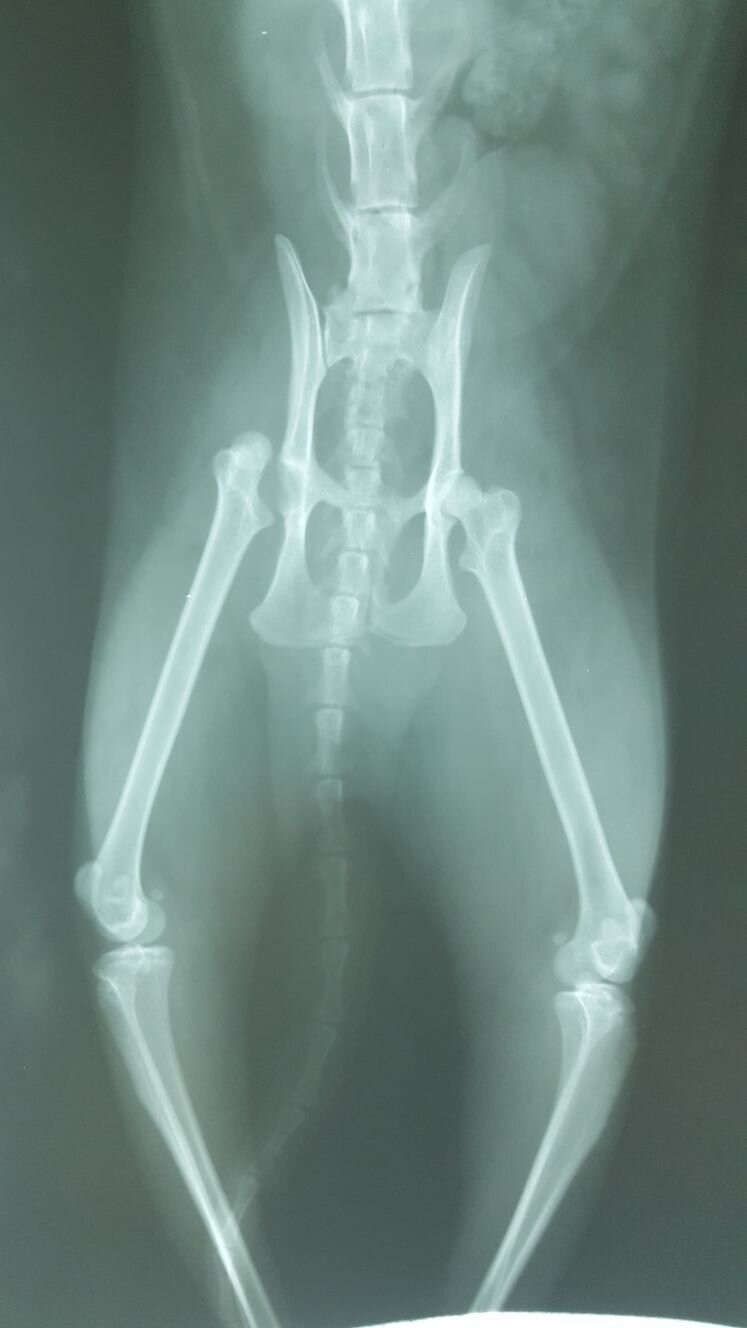

Le lussazione dell'anca nel cane e nel gatto sono in genere il risultato di un trauma esterno. Come condizione traumatica i segni clinici associati sono il dolore e movimento limitato dell'arto con presenza di crepitio. La diagnosi di lussazione può essere determinata sulla base dei segni clinici, ma per confermare la patologia é necessario eseguire radiografie dell'anca. Perla, gatto, incrocio siamese, anni due circa, femmina portata in visita per zoppia.

La scelta del metodo è in relazione al danno capsulare. Per Perla si è resa necessaria la stabilizzazione chirurgica , le foto mostrano la radiografia prima dell ' intervento, in corso di intervento e la gatta in sesta giornata post intervento. Perla ha iniziato a poggiare correttamente l ' arto a terra in quarta giornata post intervento.